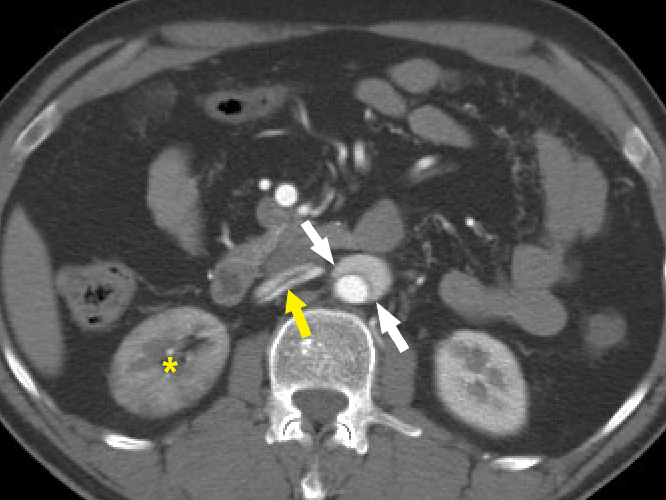

Figure 9 Beak sign of aortic dissection. Axial CT angiography image demonstrates the “beak sign” (white arrows) as an acute beak-like angulation formed by the false lumen. The dissection flap is seen extending into the right renal artery (yellow arrow). The right kidney is seen to enhance lesser (yellow asterisk) compared to the left kidney.